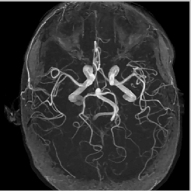

Refer to caption

(a) Circle of Willis

(b) Spine

(c) Brain3

(d) Brain4

(e) NLS,SNR=24.01

(f) NLS,SNR=29.43

(g) NLS,SNR=25.65

(h) NLS,SNR=24.75

(i) Error

(j) Error

(k) Error

(l) Error

Figure 7: Comparison of different MR images using NLS algorithms in the presence of noise. We consider the recovery from a three fold undersampled radial sampling pattern, contaminated by zero mean complex Gaussian noise with standard deviation σ=10𝜎10\sigma=10. The top two rows show the original and reconstructed images, while the error images scale by a factor of five are shown in the bottom row. We observe that the NLS scheme preserves well the edges and the fine details at low acceleration with presence of noise.